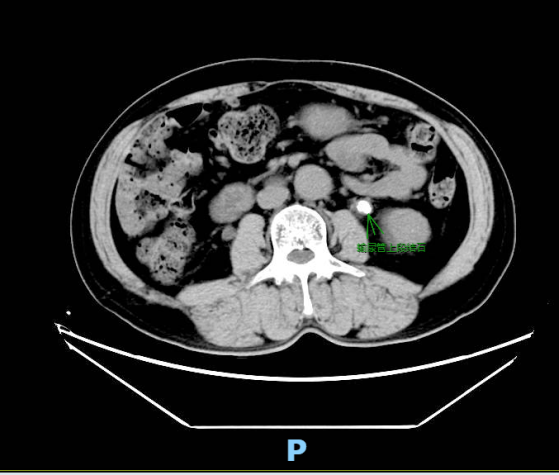

邱大叔今年60岁,是一名饱受泌尿系统疾病折磨的患者。一个月前,他开始在无明显诱因下出现进行性加重的尿频、尿急、尿痛,经外院治疗无果后转入我院普外、泌尿外科治疗。入院后经检查,确诊:左输尿管上段结石、左肾结石伴有积水和感染、双肾盂结石并轻度积水、前列腺增生。

▲输尿管上段结石